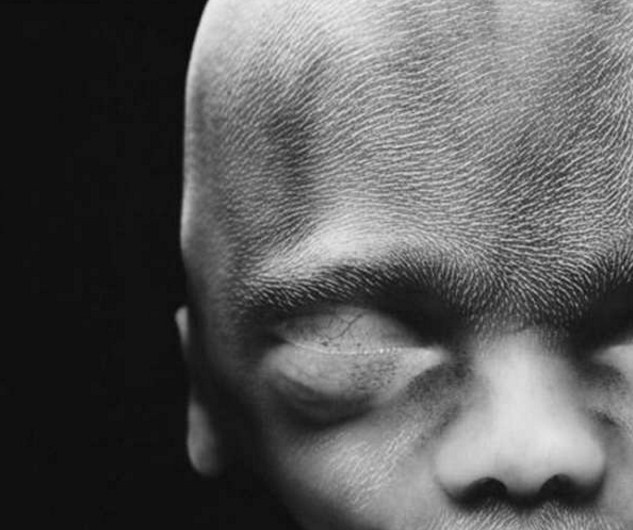

10 седмици. Клепачите вече са наполовина отворени. След няколко дни ще са напълно оформени.

На 10 седмици ембрионът вече използва ръцете си, за да изучава околната среда.